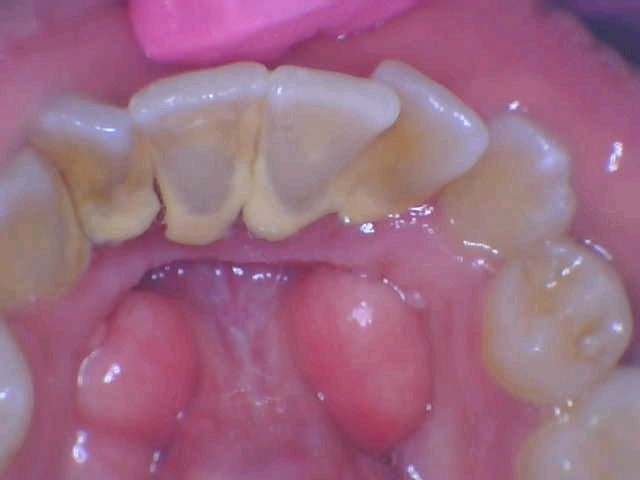

Periodontitis, also known as advanced gum disease, is a serious infection in your gums that damages your soft tissues. If not treated on time, it may destroy the bone supporting your teeth. This condition may also lead to tooth loss or loosening of your teeth from their sockets. Many factors add to the development of this disease; poor oral health is the most common of all.

- Puffy and swollen gums that appear bright red, purplish, or dusky red

- Extreme tenderness in the gums

- Bleeding from the gums

- Loosening of the teeth from their sockets

- Receding gum line